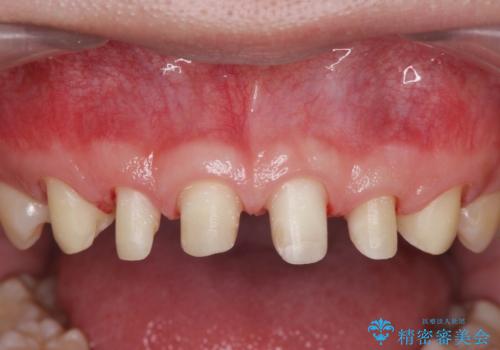

ただ、白いオールセラミッククラウンを製作・装着するのではなく、将来にわたり安定した状況を獲得するため、歯周外科を行い歯ぐきと周囲の歯槽骨の形態を整えていきます。

歯周外科を行ったことで、歯ぐきの形態や腫れが改善され、審美性だけでなく清掃性も大きく改善することができました。